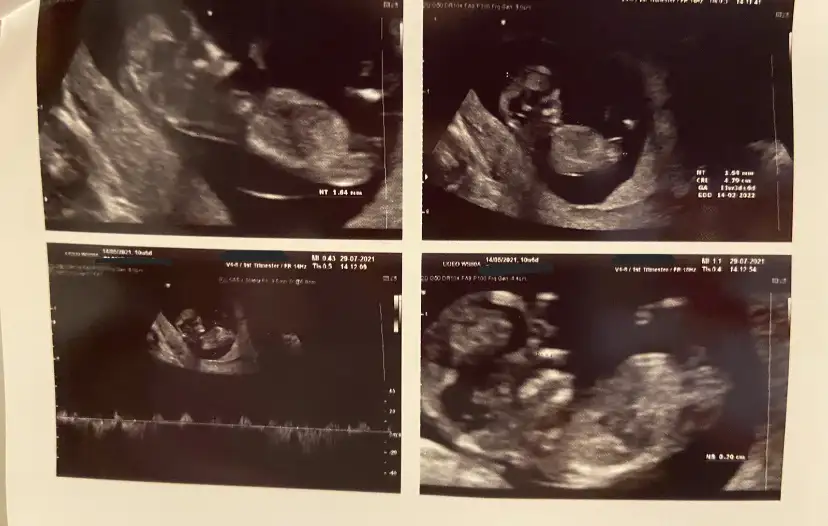

11+3 ultrasonuna göre tahmininiz nedir?10 haftaya göre kız ama en iyi 11 12 13 haftalar olmalı tekrar USG paylasin![]()

11+3 e göre tahmininiz nedir?10 haftaya göre kız ama en iyi 11 12 13 haftalar olmalı tekrar USG paylasin![]()

Kız görünüyor